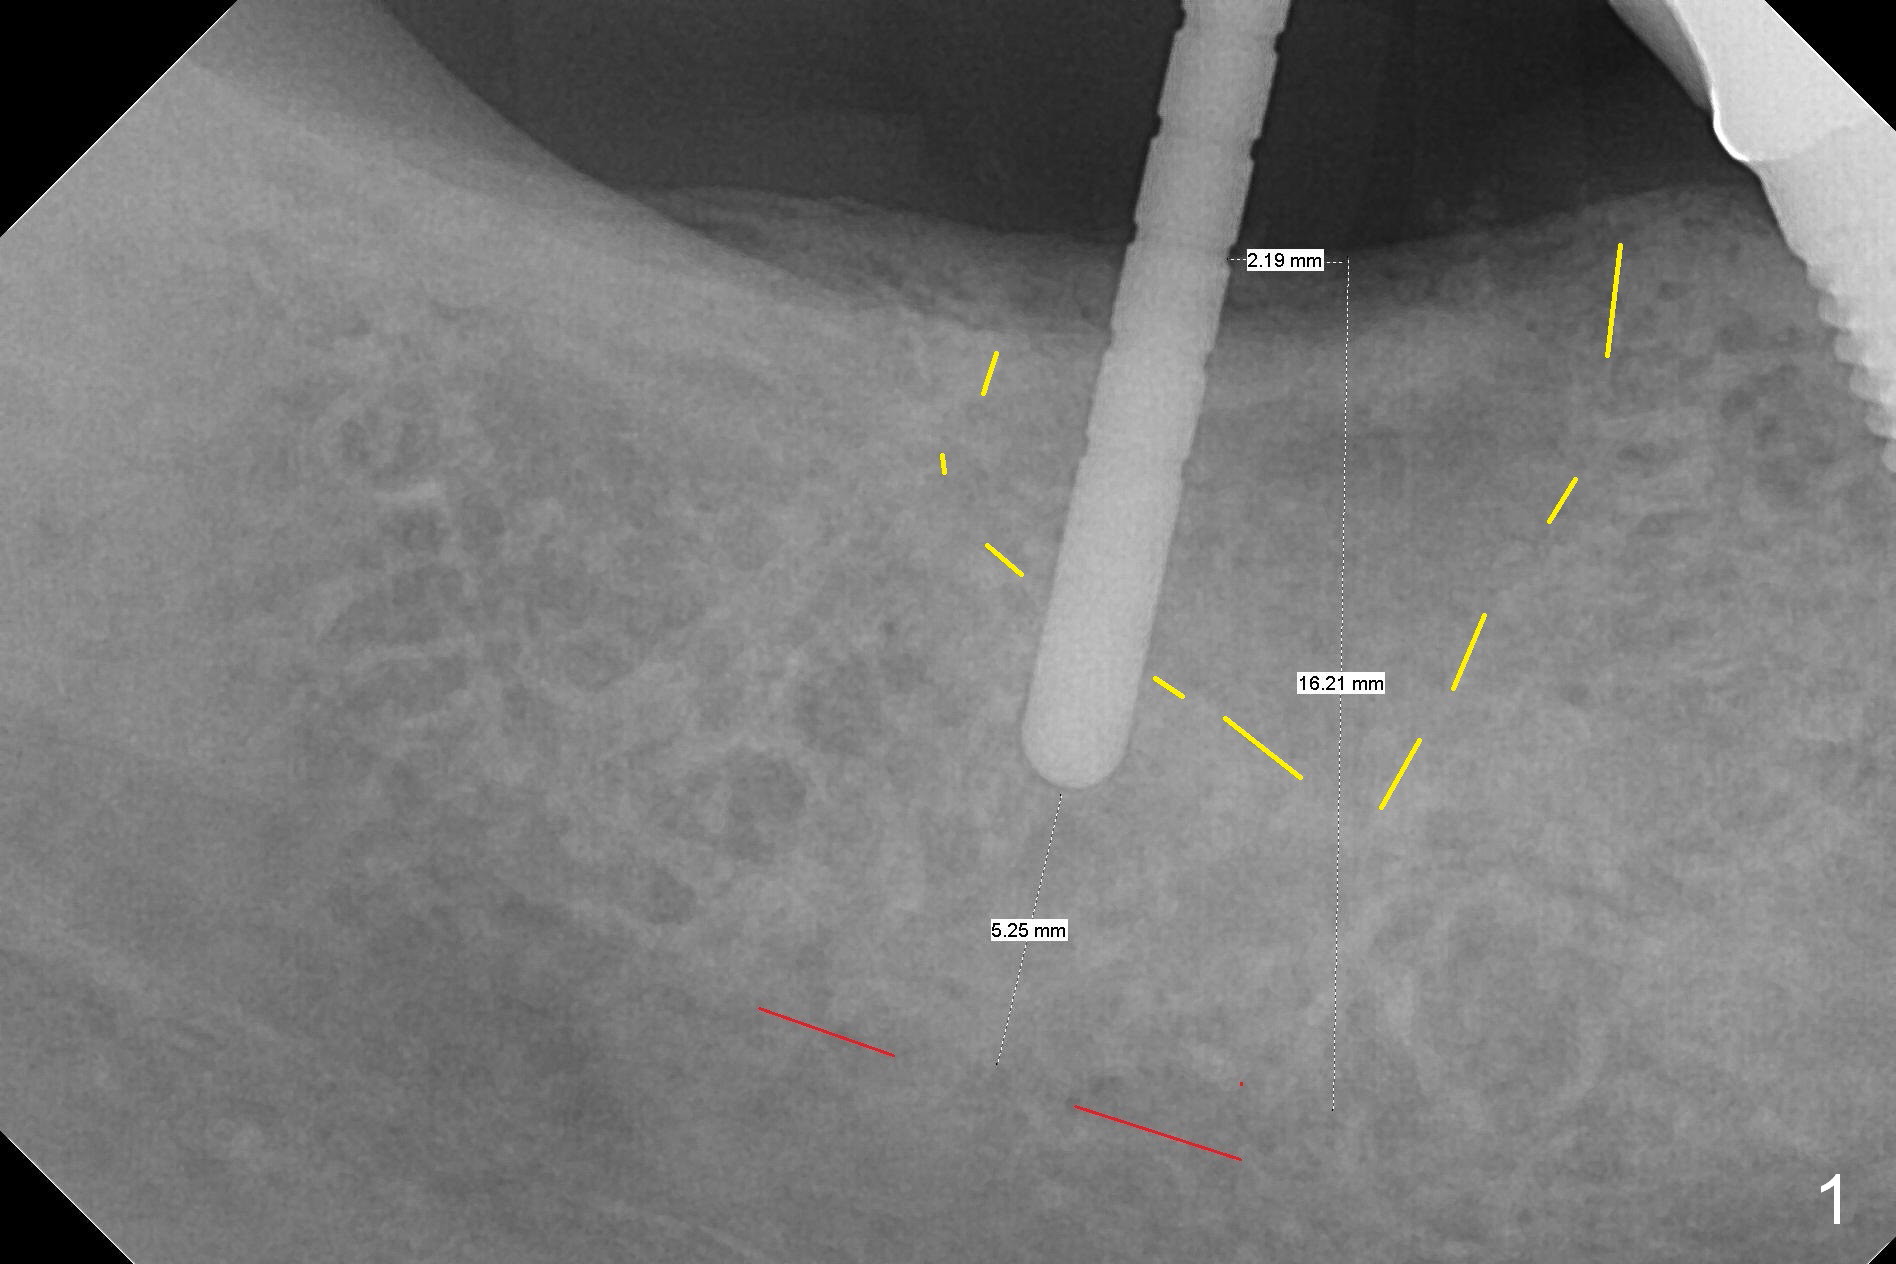

Initial osteotomy at the site of #31 using 2 mm pilot drill for 11 mm appears to be distal by 2-3 mm (Fig.1, Fig.10 A (circle, occlusal view of the edentulous and dentate (#29 and 30) areas)). Lindamann bur is used to move the osteotomy (Fig.8 white rectangle, Fig.10 B). It seems that the osteotomy returns distal as the osteotomy increases (Fig.2 (5x17 mm tap), Fig.8 arrow, Fig.10 C (green circle)). It appears to be late to change; a 5x17 mm tissue-level implant is placed with > 60 Ncm (Fig.3-5). The buccal and lingual rough surface of the implant (Fig.5 *) is covered by autogenous bone/Osteogen and Collagen Dressing (Fig.6 *). After suturing (Fig.7), periodontal dressing is applied around the abutment (Fig.5 A (4.5x3 mm)).